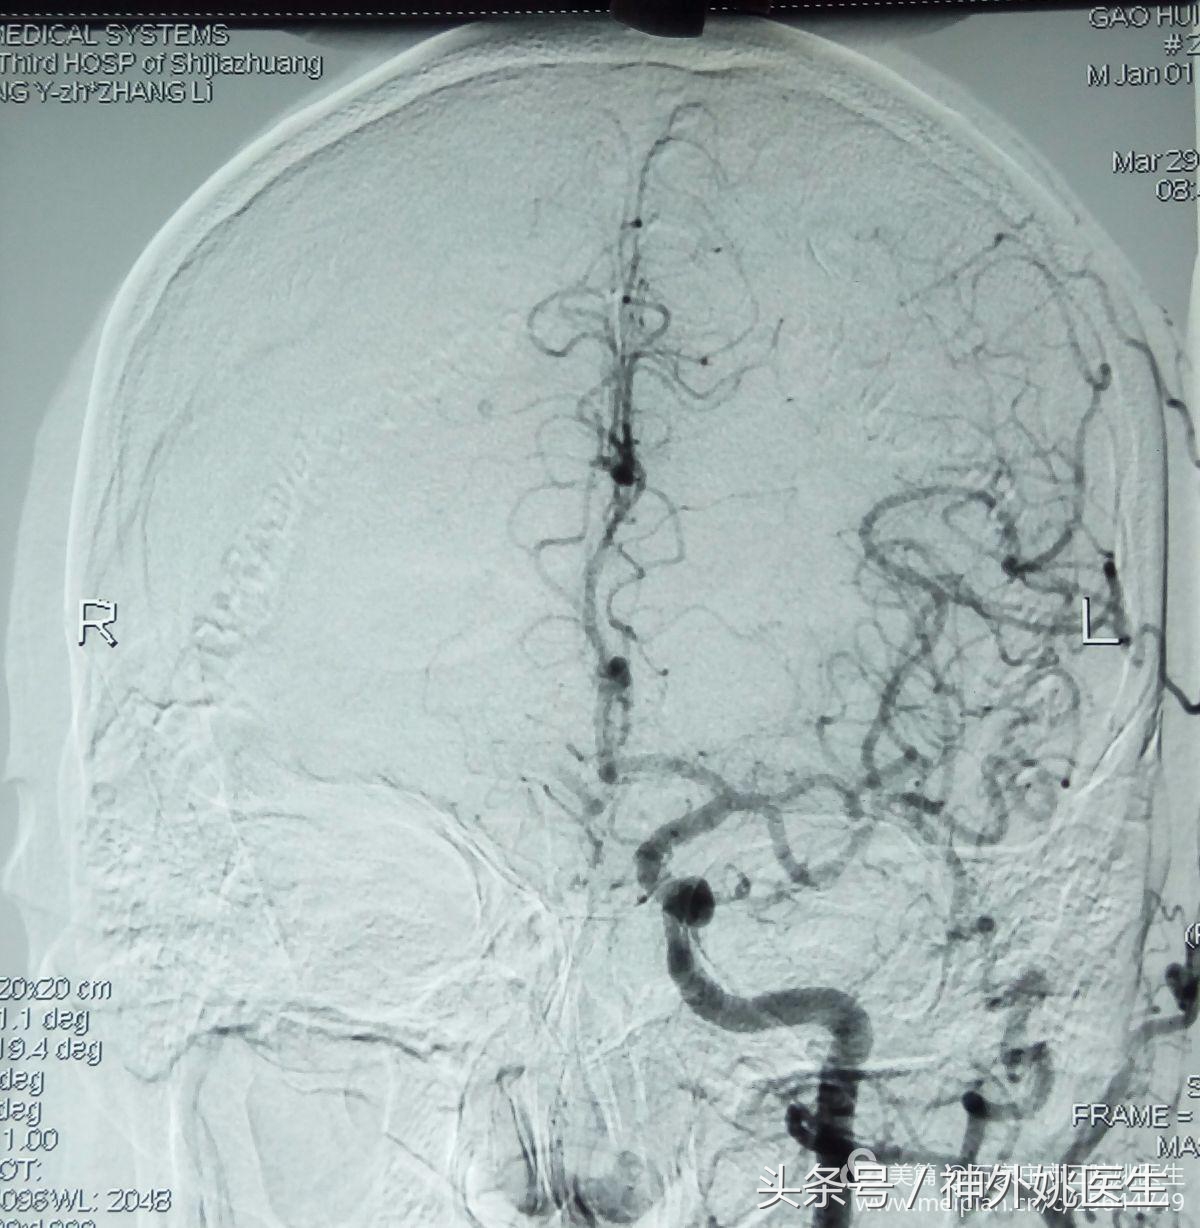

术前评估(DSA):

1.右颈动脉造影示:右颈内动脉狭窄部位位于球部以远,狭窄远端管腔明显变细(图6、图7)。狭窄段远端平下颌角及C2/3椎间盘水平(图8)。提示位置较高,操作难度较大。缝合时需精细操作,避免管径丢失,术后管腔狭窄。

图6

图7

(图8)